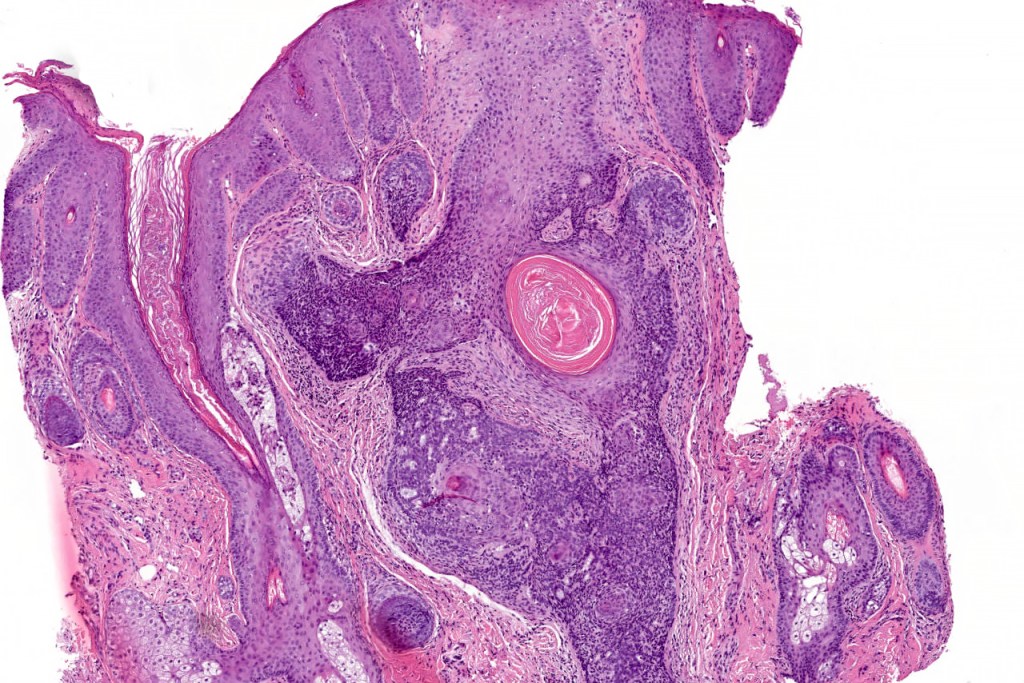

Histological features

•The classical appearance consists of keratocysts & lobules of basaloid cells

•Variable continuity with the epidermis

•Basaloid lobules show peripheral palisading

•Perifollicular mesenchyme is always conspicuous and sometimes densely aggregated are seen indenting the baslaloid lobules (papillary mesenchymal bodies)

•Narrow epithelial strands arising from the basaloid lobules are often present

•Amyloid, foreign body granuloma formation to free keratin & calcification are variable features

Trichoepithelioma should be distinguished from trichoblastoma since the latter is very rarely syndromic. Trichoepithelioma is largely a dermal tumor whereas trichoblastoma often extends from the dermis into subcutaneous fat or deeper in very large examples. Papillary mesenchymal bodies are much better formed and generally more obvious in trichoepithelioma. Trichoepithelioma must also be distinguished from basal cell carcinoma. Retraction artifact & stromal mucin are features of basal cell carcinoma and not trichoepithelioma. Papillary mesenchymal bodies are not seen in basal cell carcinoma.